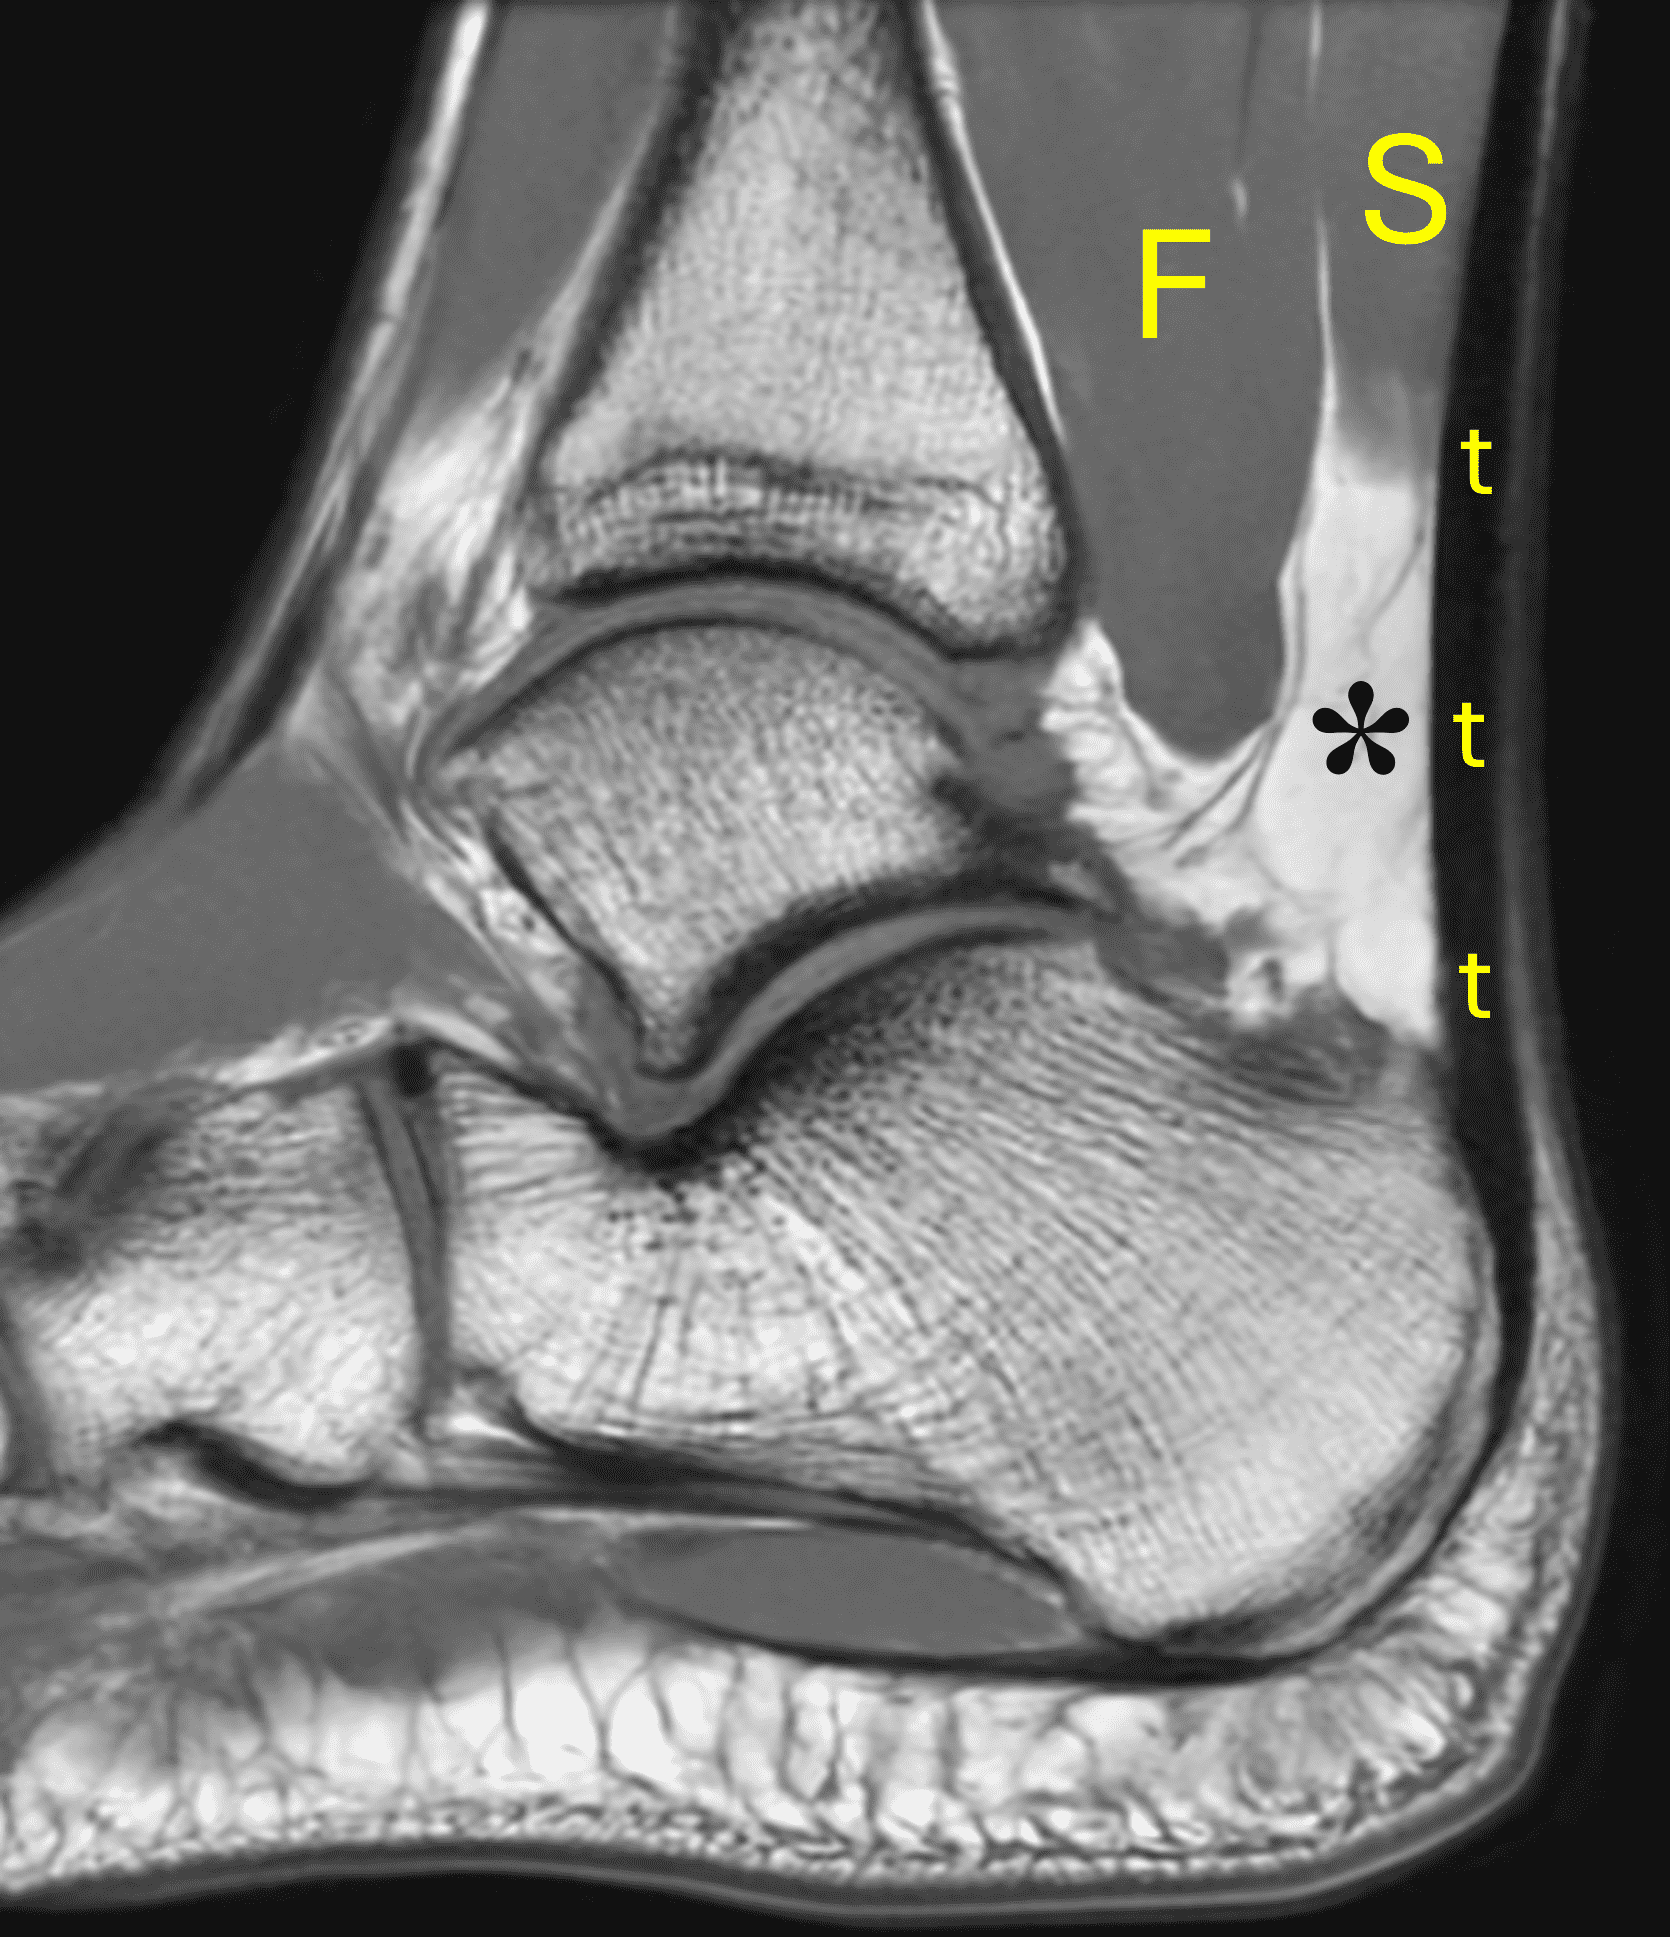

On MR images, the normal Achilles tendon demonstrates low signal intensity on all sequences (Figure 4). On sagittal images, the tendon should be uniform in thickness and have a sharp anterior margin where it abuts Kager’s fat pad. High-resolution images may reveal fine punctate or linear intermediate signal from normal interfascicular septa, especially in the distal tendon, which should not be misinterpreted as tendinosis, particularly when the tendon thickness is normal.6 When the tendon fibers are oriented near to 55° with respect to the B0 magnetic field, increased signal may be seen on short-TE sequences due to the magic angle effect, with decreasing artifact on longer-TE sequences. MR images obtained at higher field strengths (3-7 T) accentuate the fascicular detail and normal septations as well as magic-angle effects.5,6 On transverse images, the posterior tendon margin is typically convex; the anterior margin is flat-to-concave along most of its length but may be focally convex at the gastrocnemius–soleus convergence, which is considered a normal variant. The average tendon thickness is approximately 6 mm, with variation by body size, age, and sex.20

The normal Achilles paratenon appears as a thin low-to-intermediate signal rim.6 The retrocalcaneal bursa lies between the distal tendon and calcaneus and normally contains only minimal fluid. The contents of Kager’s fat pad should be isointense to fat on all pulse sequences, with traversing vessels and thin fascial strands that should not be mistaken for pathology.

Figure 4: MRI appearance of the normal Achilles tendon. (4A) Sagittal T1-weighted image shows the low signal intensity Achilles tendon (t) with uniform thickness. Kager’s fat pad (asterisk) normally contains thin fibrous strands and vessels. S = soleus muscle, F = flexor hallucis longus muscle. (4B) Sagittal fat-suppressed fluid-sensitive sequence shows the sharp anterior tendon margin (arrowheads) and a physiologic amount of fluid in the retrocalcaneal bursa (arrow). (4C) Transverse T1-weighted image just proximal to its insertion shows the Achilles tendon (yellow arrow) with a concave anterior margin and convex posterior margin. The much smaller plantaris tendon (red arrow) lies along the anteromedial margin of the Achilles. (4D) Transverse fat-suppressed T2-weighted image shows punctate foci of higher signal intensity (arrowhead) in the distal tendon representing normal interfascicular septa.